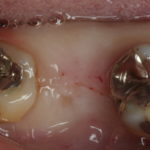

この患者さんは30代の女性で、歯が割れてしまったので抜歯してインプラントにしました。抜歯後の骨の再生を促すために、PRGFを行っていますので、通常より早く骨が再生したため良好な結果が得られています。

このケースではインプラントを入れる時にほとんど歯肉を切っていません。こういった手術ができれば、まず張れや痛みはありません。インプラントの手術は、安全な治療計画を立て、確実な技術があれば、本当に痛みはありません。